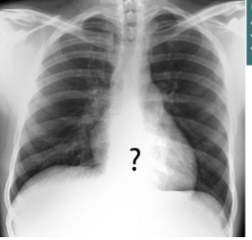

Label this CXR (10 things)

1) trachea 2) hilum- should have R and L 3) lungs 4) diaphragm 5) heart 6) aortic knuckle 7) ribs 8) scapulae 9) breasts 10) bowel gas